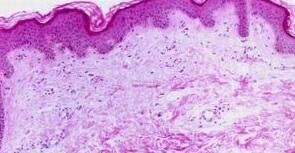

过敏荨麻疹病因有哪些?过敏性荨麻疹就是大家耳熟能详的皮肤病,当然荨麻疹患者当中大约四个人之中就有一个人曾经为它所困扰着。那么下面就请北京京城皮肤医院为您具体的讲解一下吧。希望能给患者带来一定的帮助!

北京京城皮肤医院指出,临床上,此病好像千面女郎般,可以以不同的面貌呈现出來。荨麻疹病就目前来讲,某些表现型是与*机制有密切的关系,尤其是那些被认为和*蛋白E有关者,而另有某些表现型则是机制上没有较好的答案。

当然荨麻疹发作大多数是短暂性的,而且是会发展到某一种程度就自动停止发展,一般表现在儿童较多。